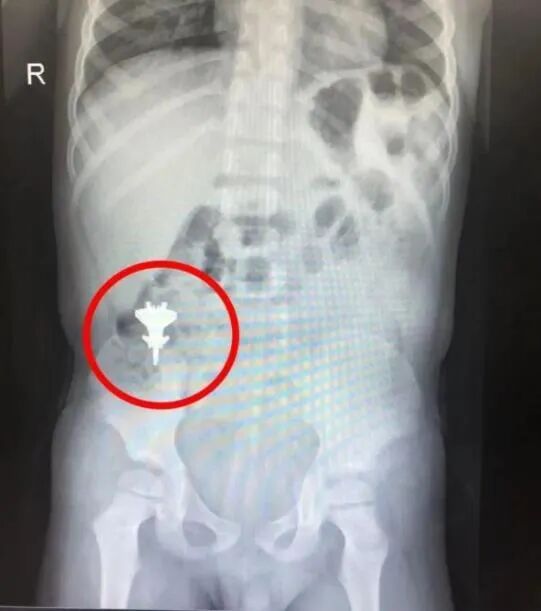

当医生给他拍片的时候都惊呆了,拍出来的片子居然清晰地看到孩子肚子里有一架“歼-20”玩具飞机!

而这个飞机是“歼-20”玩具飞机模型,金属质地,长度约为3CM。

(玩具飞机在男孩体内)

主治医生考虑到这孩子年龄较小,消化道进入异物可能会造成消化道的穿孔、出血等危险,但也有一定的概率能自行排出,便让家长密切观察孩子病情变化,通过吃流质食物、口服石蜡油等方法,促进异物自行排出,同时,让他们定期回来复查拍片,了解小飞机在体内的运动轨迹。

所幸,通过连续几次腹部拍片复查,小飞机模型在孩子身体里绕了一圈,2天后,成功从肛门自行排出。